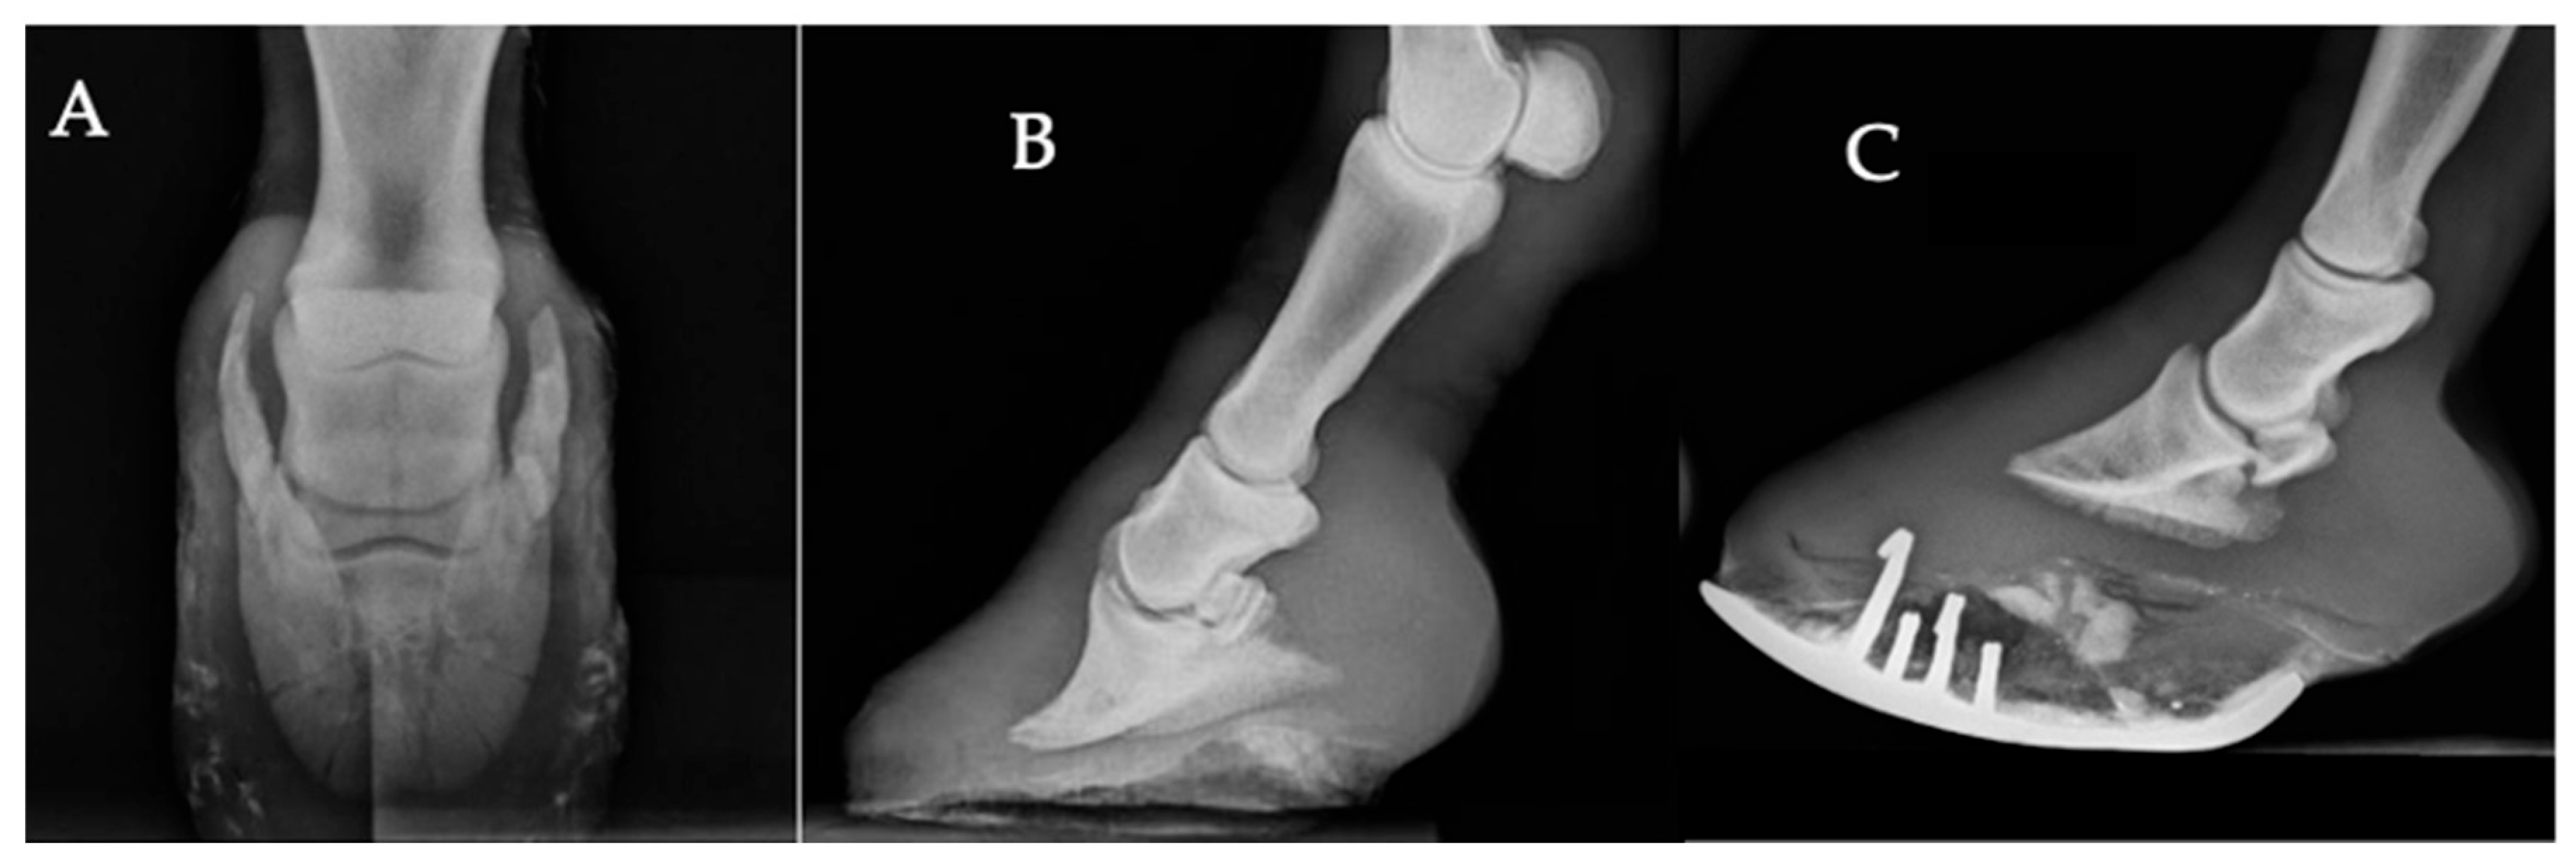

- Foot-related changes. Radiographs were included when they showed podiatric abnormalities such as ossification of the ungular cartilages, abnormal hoof conformation (e.g., excessively long toe, low or underrun heels), or laminitic changes (increased distance between the dorsal hoof wall and the distal phalanx, dorsal distal phalanx modeling, or rotation). Changes affecting the solar border of the distal phalanx were described as solar margin remodeling, which could include an irregular contour, blunting, or focal areas of bone lysis visible on radiographs, and did not meet the radiographic criteria for laminitis. Fractures involving the foot were excluded from this category and classified separately. Changes in the hoof capsule were described as associated morphological features and were not considered primary osseous lesions.

- Subluxation/Luxation. Partial or complete displacement of articular surfaces relative to one another, confirmed on orthogonal projections.